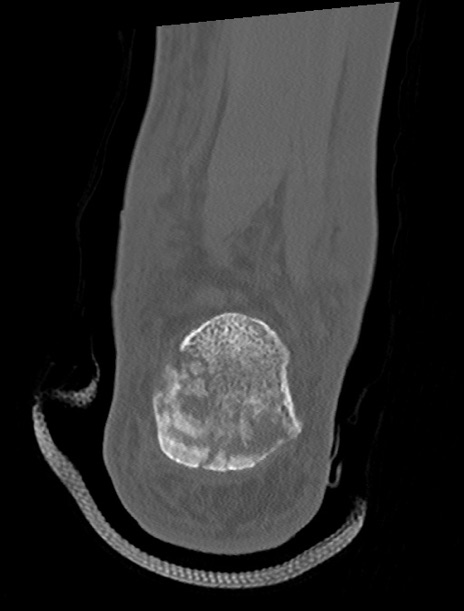

矢状断像